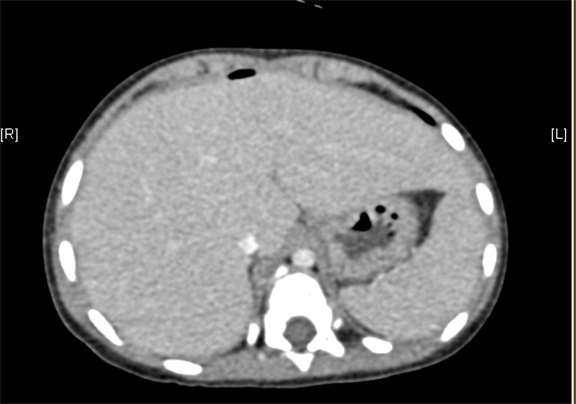

术前CT检查:

动脉期

上腹部增强CT提示肝门处占位性病变,考虑腹膜后肿瘤可能性大,畸胎瘤? AFP 11.38ng/ml

将0.625mm双源薄层CT资料的静脉期和动脉期Dicom格式文件导入海信CAS系统。

通过调节窗宽窗位调整CT序号,对肿瘤、肝实质,胆囊,下腔静脉,肿瘤,肝动脉、门静脉及肝静脉等进行三维重建;系统自动计算肿瘤体积和肝脏体积。